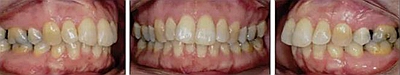

患者曾行正畸治療,現(xiàn)覺(jué)笑容不美觀前來(lái)就診。患者正面觀及側(cè)貌示下頜發(fā)育不足,偏高角,唇閉合不全。上下頜中線齊。覆合、覆蓋4毫米。磨牙關(guān)系及尖牙關(guān)系II類(lèi)。上頜擁擠度4mm,下頜擁擠度6mm。4顆第一前磨牙在第一次正畸治療時(shí)已拔除。上下牙弓呈尖圓型,牙弓狹窄。

患者側(cè)貌改善,下唇唇肌緊張消失,上下唇可自然閉合。磨牙及尖牙關(guān)系糾正至I類(lèi),覆合覆蓋正常。上下頜弓型糾正至卵圓形,牙弓寬度增加。頭影測(cè)量分析示SNA角81.8°,ANB角3°。頭影測(cè)量重疊圖示下頜骨向后旋轉(zhuǎn),垂直面高度略有增加。